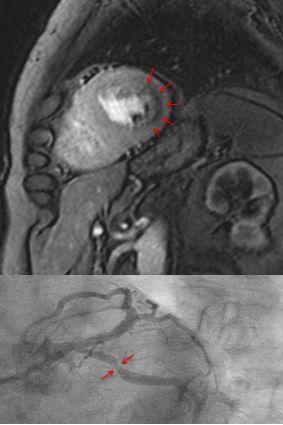

image: Measuring blood flow in the myocardium with magnet resonance imaging (top). The dark area in the myocardium (arrows) shows a pronounced reduction of blood flow. The cardiac catheterization of the same patient (bottom) shows a clear constriction of the artery.

For patients with chest pain and presumably stable coronary heart disease (CHD), therapy depends primarily on how constricted the arteries that support the heart are (coronary arteries). This is often determined using an invasive procedure called cardiac catheterization. If necessary, the pressure in the coronary arteries is also measured. The combination of these methods is the currently the recognized standard for making therapy decisions. Cardiovascular magnetic resonance imaging (MRI) is an alternative for directly measuring the blood flow in the myocardium.